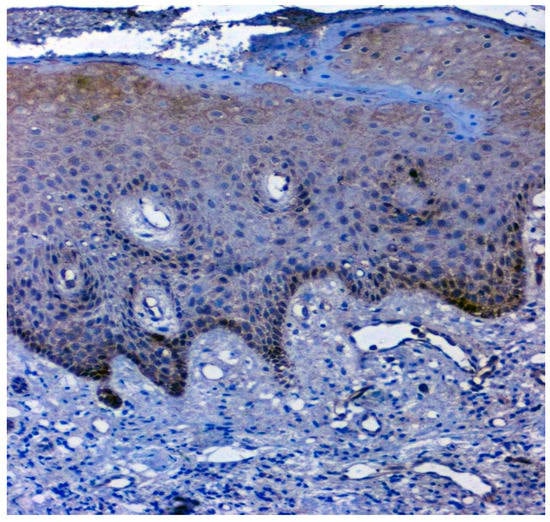

Figure 7.

IHC for 14-3-3ε in normal samples (under 20× magnification).

The expression of 14-3-3ε was studied in 130 patients, of which 81.5% (106/130) were found to be expressing 14-3-3ε. There was a significant correlation (p = 0.000; χ2 = 33.600) with expression among normal vs. OSMF vs. OSMF vs. OSCC patients. Table 4 shows the details of 14-3-3ε expression, which correlated with clinicopathological parameters. We found a statistically significant overexpression (p = 0.019; χ2 = 5.496) with increased age (>43 years), atrophic epithelium (p = 0.011; χ2 = 13.149) and increased degrees of inflammation (p = 0.041; χ2 = 8.252). Figure 7 shows the negative immunoexpression of 14-3-3ε in normal samples. Figure 8 shows the 14-3-3ε-positive immunoexpression in epithelial cells in OSMF samples, with cytoplasmic and nuclear positivity. In OSCC samples, 14-3-3ε demonstrates strong cytoplasmic and nuclear positivity in malignant epithelial cells (Figure 9).